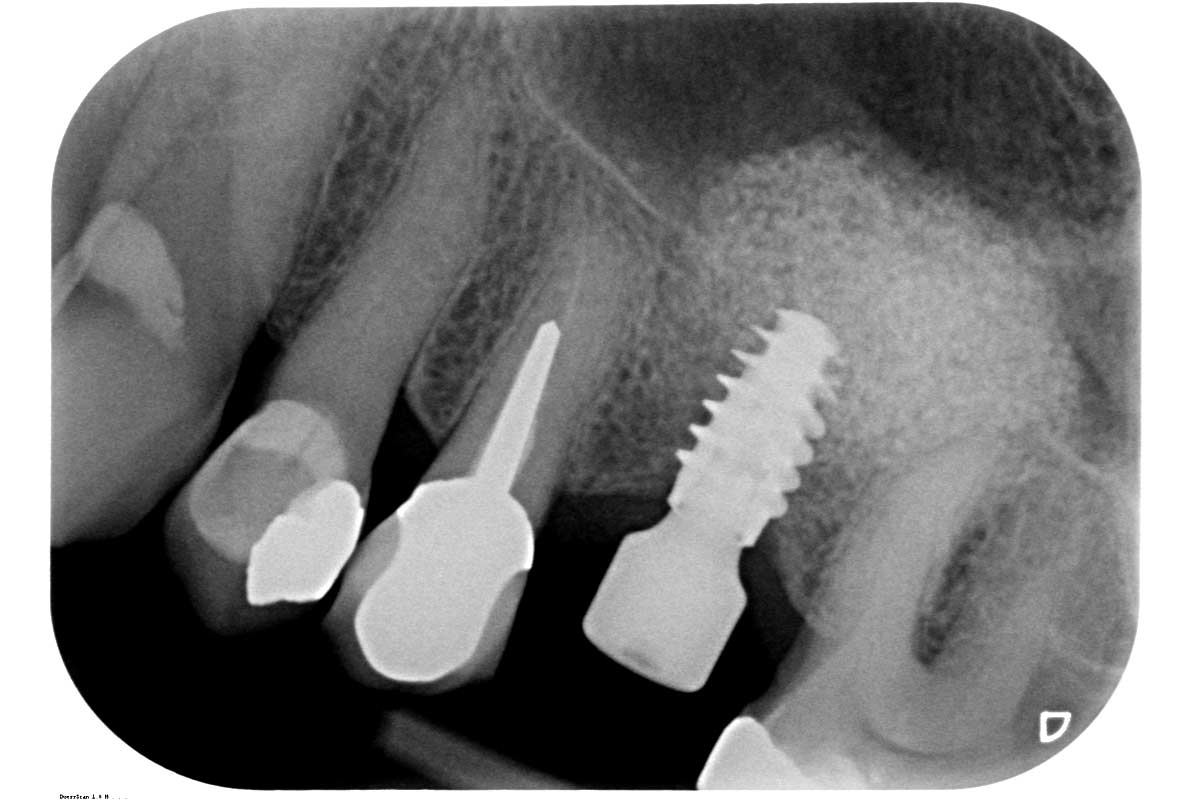

16/35 - X-ray after 5 monthsMaxillary sinus cyst removal using the Crocodile Technique and subsequent lateral sinus lift - Dres. C. Scognamiglio and A. Perucchi